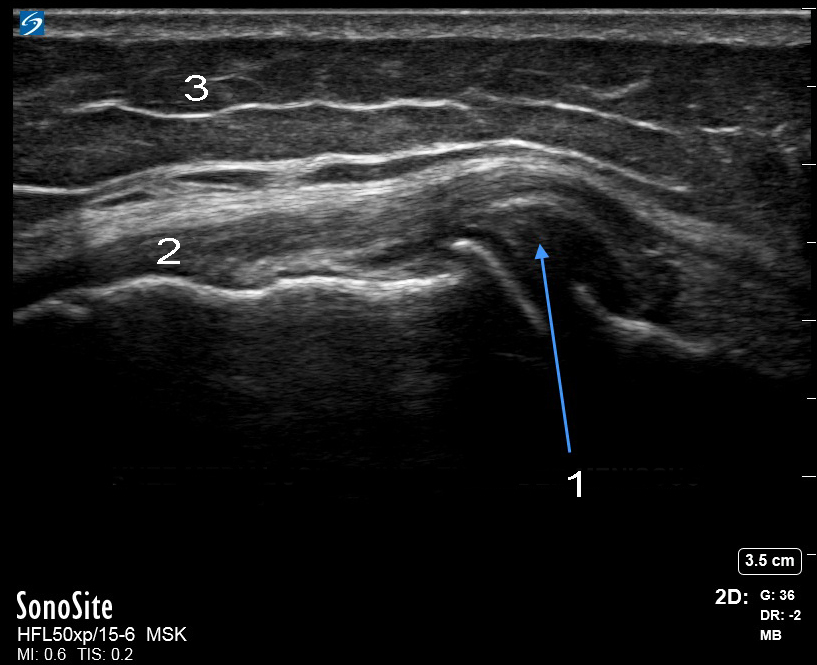

膝内側半月板押出画像

内側の継ぎ目 - 押し出しメニスカス

内側側副靱帯(MCL)

脂肪